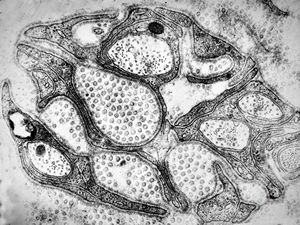

F,8y. | metachromatic leukodystrophy - n.suralis

F,25y. | metachromatic leukodystrophy - n.suralis

F,8y. | metachromatic leukodystrophy - n.suralis

F,25y. | metachromatic leukodystrophy - n.suralis

F,25y. | metachromatic leukodystrophy - n.suralis